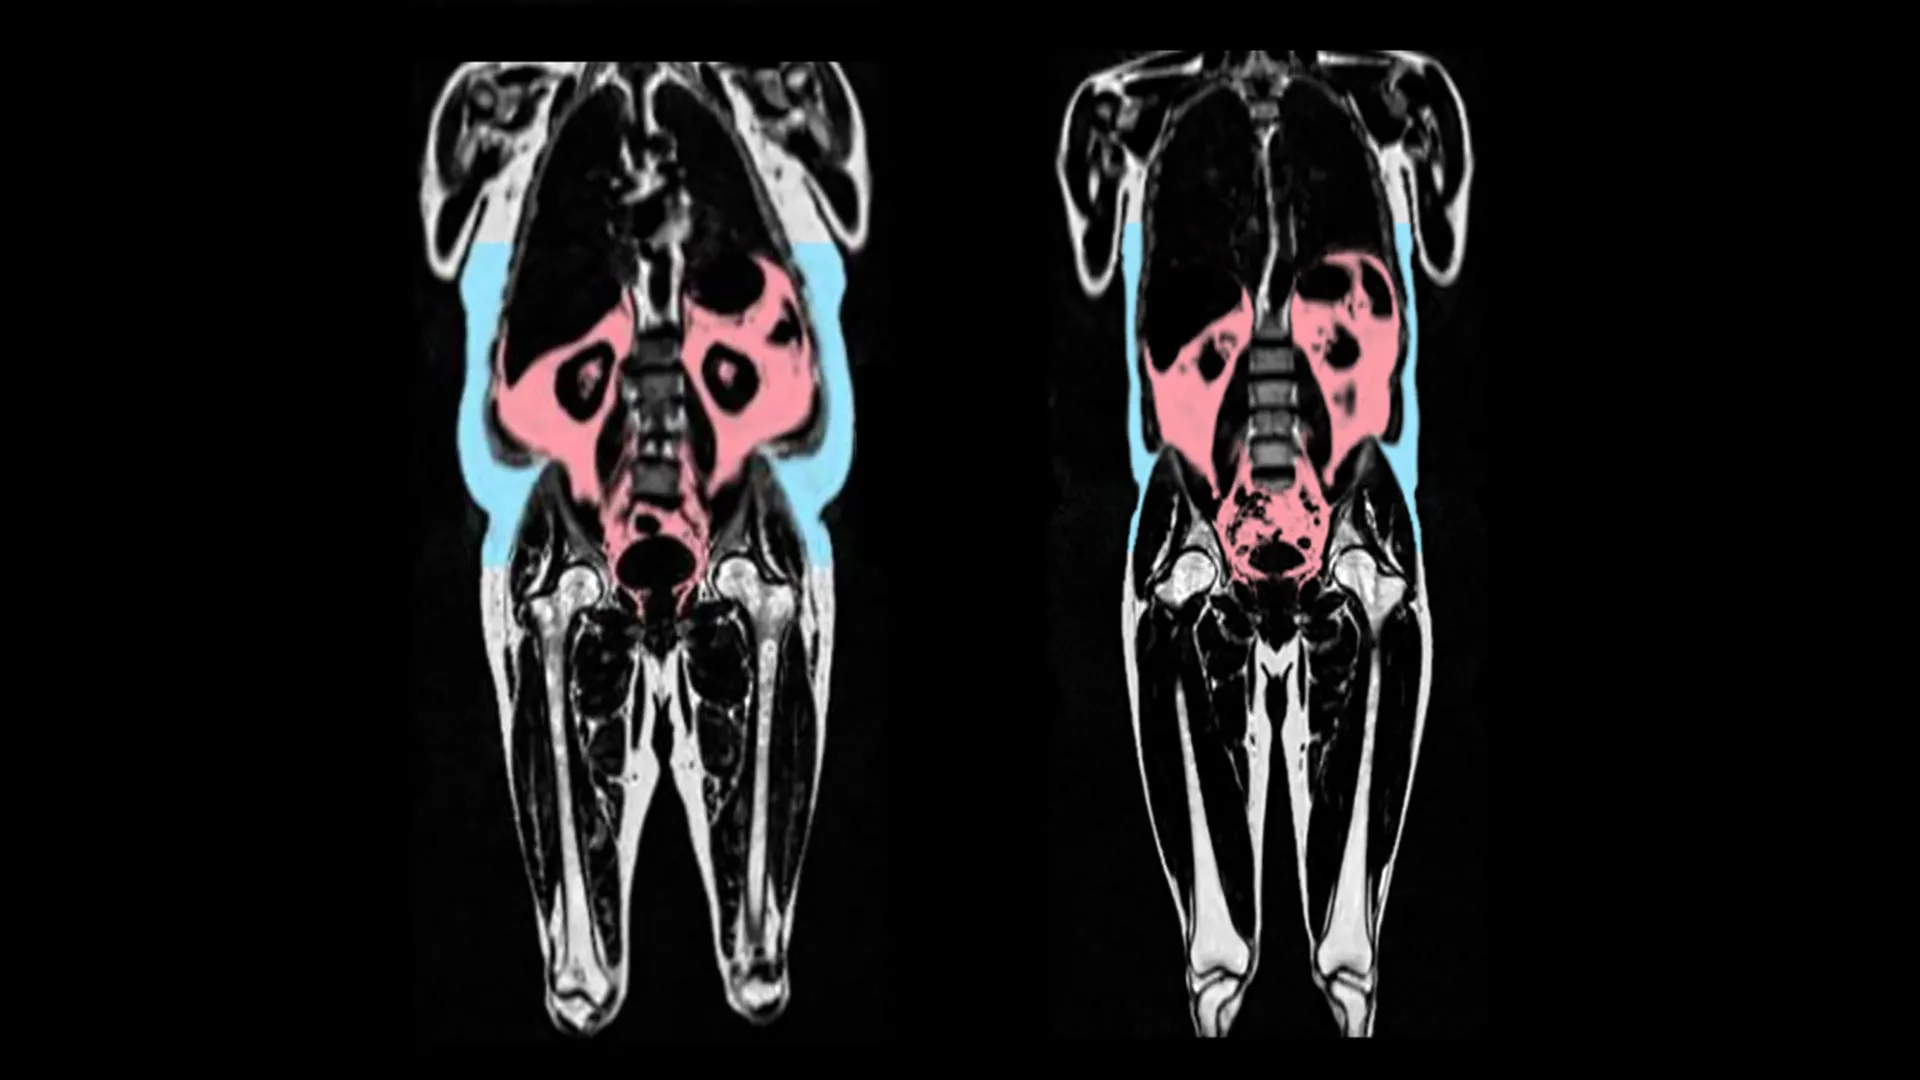

No estudo, publicado no European Heart Journal, os cientistas analisaram dados de 21.241 participantes no UK Biobank, que inclui imagens do corpo inteiro para mapear a quantidade de gordura e onde ela está localizada no corpo.

Os dados do UK Biobank também incluem imagens detalhadas do coração e dos vasos sanguíneos. A inteligência artificial foi utilizada para analisar essas imagens e capturar sinais de envelhecimento dos órgãos — como tecidos se tornando rígidos e inflamados. Um indivíduo recebeu uma “idade cardíaca” que pode ser comparada à sua idade real no momento do exame.

Os pesquisadores descobriram que o envelhecimento mais rápido do coração estava ligado a ter mais tecido adiposo visceral. O tecido adiposo visceral é gordura encontrada profundamente dentro do abdômen ao redor de órgãos como estômago, intestinos e fígado. Esse tipo de gordura não pode ser visto de fora, e algumas pessoas podem ter grandes quantidades de gordura visceral, apesar de terem um peso saudável.

Eles também notaram diferenças entre os sexos. A distribuição de gordura do tipo masculino (gordura ao redor da barriga, frequentemente chamada de formato “maçã”) foi particularmente preditiva de envelhecimento precoce em homens.

Em contraste, uma predisposição genética para gordura do tipo feminino (gordura nos quadris e coxas, frequentemente chamada de formato “pera”) foi protetora contra o envelhecimento do coração nas mulheres.